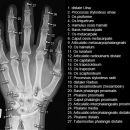

Hand a.p. (dorsovolar)

Beurteilungskriterien

• Kontinuität der drei Karpalbögen (vgl. Handgelenk):

Proximaler Bogen: proximale Gelenkflächenkonturen von Scaphoid, Lunatum und Triquetum

Mittlerer Bogen: distale Gelenkflächenkonturen von Sacphoid, Lunatum und Triquetum

Distaler Bogen: proximale Gelenkflächenkonturen von Capitatum und Hamatum

Fehlende Abgrenzbarkeit, Versatz oder Unterbrechung sind als pathologisch zu bewerten und deuten auf eine Luxation hin.

• M-förmiger Verlauf der Gelenkspalten der Carpometacarpalgelenke? Luxationsstellung in den Carpometacarpalgelenken (meist dorsale Luxation)?

• Gelenkspaltweiten der Carpometacarpalgelenke, der Metacarpophalangealgelenke und Interphalangealgelenke 1 –2mm, der Intercarpalgelenke 1,5 – 2mm

• Täuschungsmöglichkeiten durch Vielzahl akzessorischer Ossikel (abgerundete, zirkulkär-geschlossene Kortikalis), geteilte Handwurzelknochen (Scaphoid, Lunatum, Pisiforme) und Gefäßkanälchen

• Target areas leicht zu übersehender Frakturen:Processus styloideus radii et ulnae, Basen der Metacarpalia (v.a. MCP I) -> großzügige CT-Indikation, Hamulus

Cave: Metacarpale und phalangeale Rotationsfehlstellungen sind konventionell röntgenologisch schwer zu diagnostizieren und zu quantifizieren -> klinischer Befund führend (Fingerstrahl kreuzt bei Beugung im Grundgelenk den benachbarten Strahl), evtl. CT hilfreich.